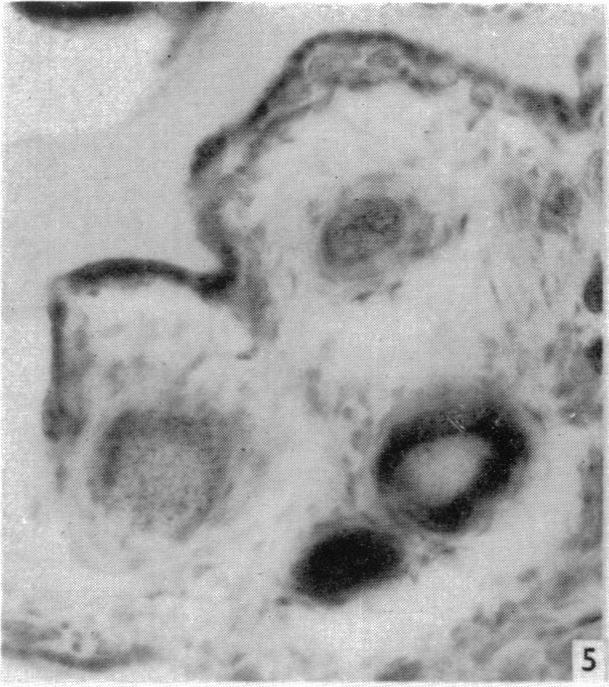

A histochemical study of placental esterases in the guinea-pig and in the human.

J Anat. 1958 Jan;92(1):110-7.